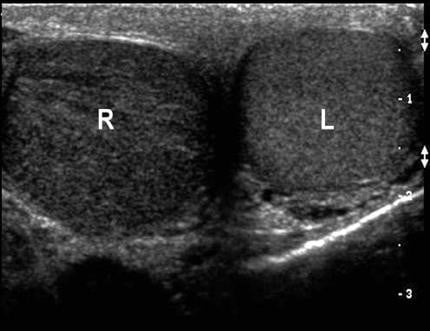

6. Then move to the “buddy view,” which is a transverse view of both testicles in the same image. Compare both testicles echogenicity, blood flow, and size. In a testicular torsion, you should see a decrease in echogenicity on the affected side (Figure 1), while in epididymitis you will generally see normal echogenicity and enlargement of the epididymis (Figure 2). Of note, echogenicity may be normal in intermittent or early torsion cases.

Figure 1. Left testicle normal with right testicular torsion and hypoechogenicity. Courtesy of Michael Blaivas, MD